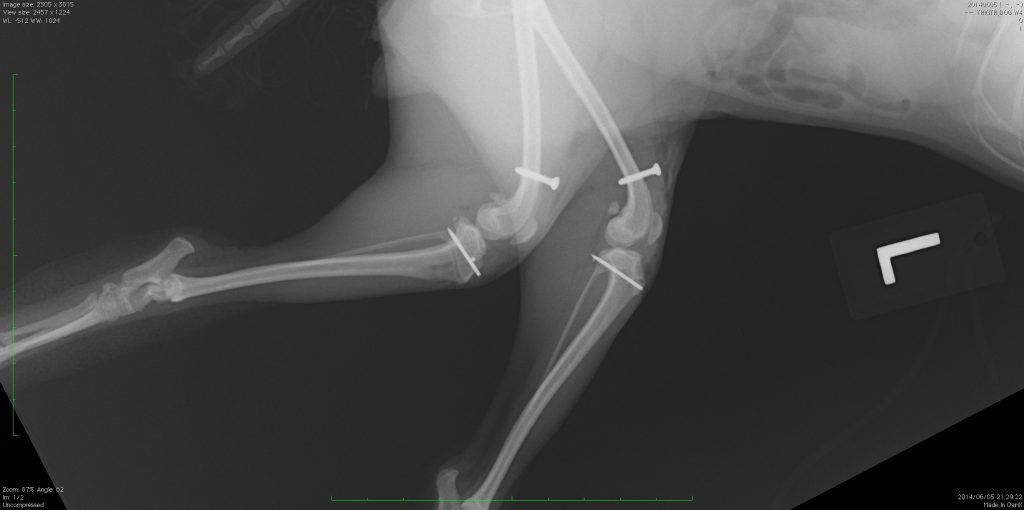

先日、犬の膝蓋骨脱臼の症例で、外科を得意とされる先輩の先生と一緒に手術させてもらう機会がありました。